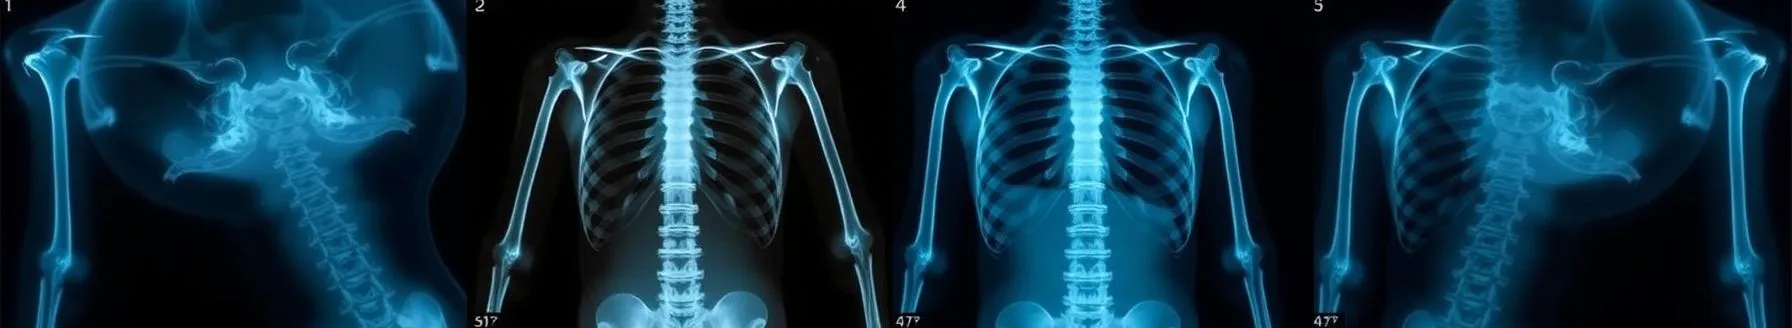

Interpreting spinal X-rays involves a systematic approach to assessing the bony structures of the spine and their alignment. Key aspects include: Analyzing the vertebral bodies' alignment along the central axis, looking for any shifts, tilts, or rotations that could indicate spinal deformities...

- Dr. Supano hosted a webinar on systematic interpretation of spinal x-rays, featuring Dr. Rakesh A. Luri, an expert in emergency medicine. The webinar focused on structured assessment and interpretation of spinal radiographs, essential for managing trauma patients and deciding on cervical spine motion restriction.